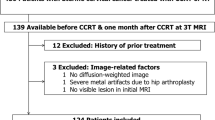

This study complied with the Transparent Reporting of a Multivariable Prediction Model for Individual Prognosis or Diagnosis (TRIPOD) Statement. We retrospectively analysed three consecutive prospectively collected cohorts from February 2007 to December 2014 (IRB 95-1243B, IRB 97-2366B and IRB 102-0620A3), enrolling all the available and evaluable cases during the study period. There was no sample size estimation at the initial stage. Our institutional review board approved this study and informed consents were obtained. The study setting was conducted in a tertiary referral centre with a dedicated interdisciplinary gynaecological oncology team. The inclusion criteria for this study were: biopsy proved newly diagnosed cervical cancer clinical stage FIGO IB-IVA and willing to undergo CCRT treatment. The exclusion criteria were: patients who are judged to be non-compliant to treatment or not accessible for follow-up, patients having contraindications to MR scanning, or patients unable to cooperate for MR study due to mental status. The patient cohort is detailed in Fig. 1. We recorded the relevant clinical information, including age, histology, grade, HPV status and serum levels of squamous cell carcinoma antigen (SCC-Ag) and carcinoembryonic antigen (CEA). Serum SCC-Ag level is elevated in 28-88% of patients with squamous cell cervical cancer, and has shown prognostic significance for patients undergoing surgical treatment or radiation therapy [16]. Data collection was planned before the MR imaging acquisition. A total of 134 evaluable subjects entered final analysis in this study; age ranged from 24 to 92 years (median, 54 years).

ADC maps were generated using a monoexponential decay model with b value of 0 and 1,000 s/mm2 (VB17a, Trio TIM; Siemens Healthineers). Anonymous data were exported offline to a personal computer. By using an in-house developed software based on Matlab (MathWorks, Natick, MA, USA), the first reader (Y.T.H, a gynaecological radiologist with 8 years of experience) drew regions of interest (ROIs) around the tumour on each slice on the ADC maps with reference to the high b value DW and T2-weighted images to delineate the whole tumour volume to minimise the slice selection bias. The second reader independently verified the ROIs (G.L., a gynaecological radiologist with 10 years of experience). Both readers were blinded to clinical outcome. Care was taken to avoid non-pathological structures in the ROIs, such as normal cervical stroma, vascular structures, fluid or Nabothian cysts in the cervix. The mean, minimum, 10th, 25th, 50th, 75th and 90th percentiles and maximal pixel ADC values (ADCmean, ADCmin, ADC10, ADC25, ADC50, ADC75, ADC90 and ADCmax, respectively) were generated, and the skewness and kurtosis of the histogram were recorded (Fig. 2). The tumour volume was calculated by multiplying the voxel size of DW image by the number of voxels in the ROI, where the voxel size = in-plane pixel size (1.5625 mm2) × (4 mm slice thickness + 1 mm gap) = 7.8125 mm3.